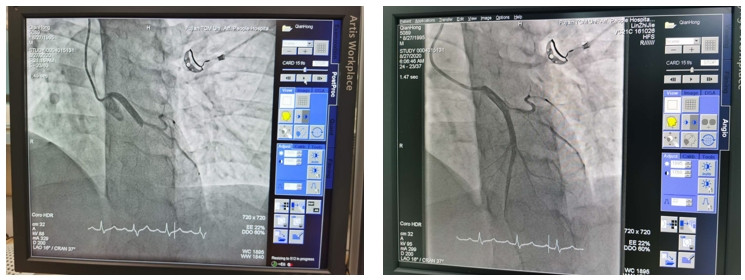

急性心肌梗死急診介入

急性心肌梗死急診介入血栓抽吸術(shù)